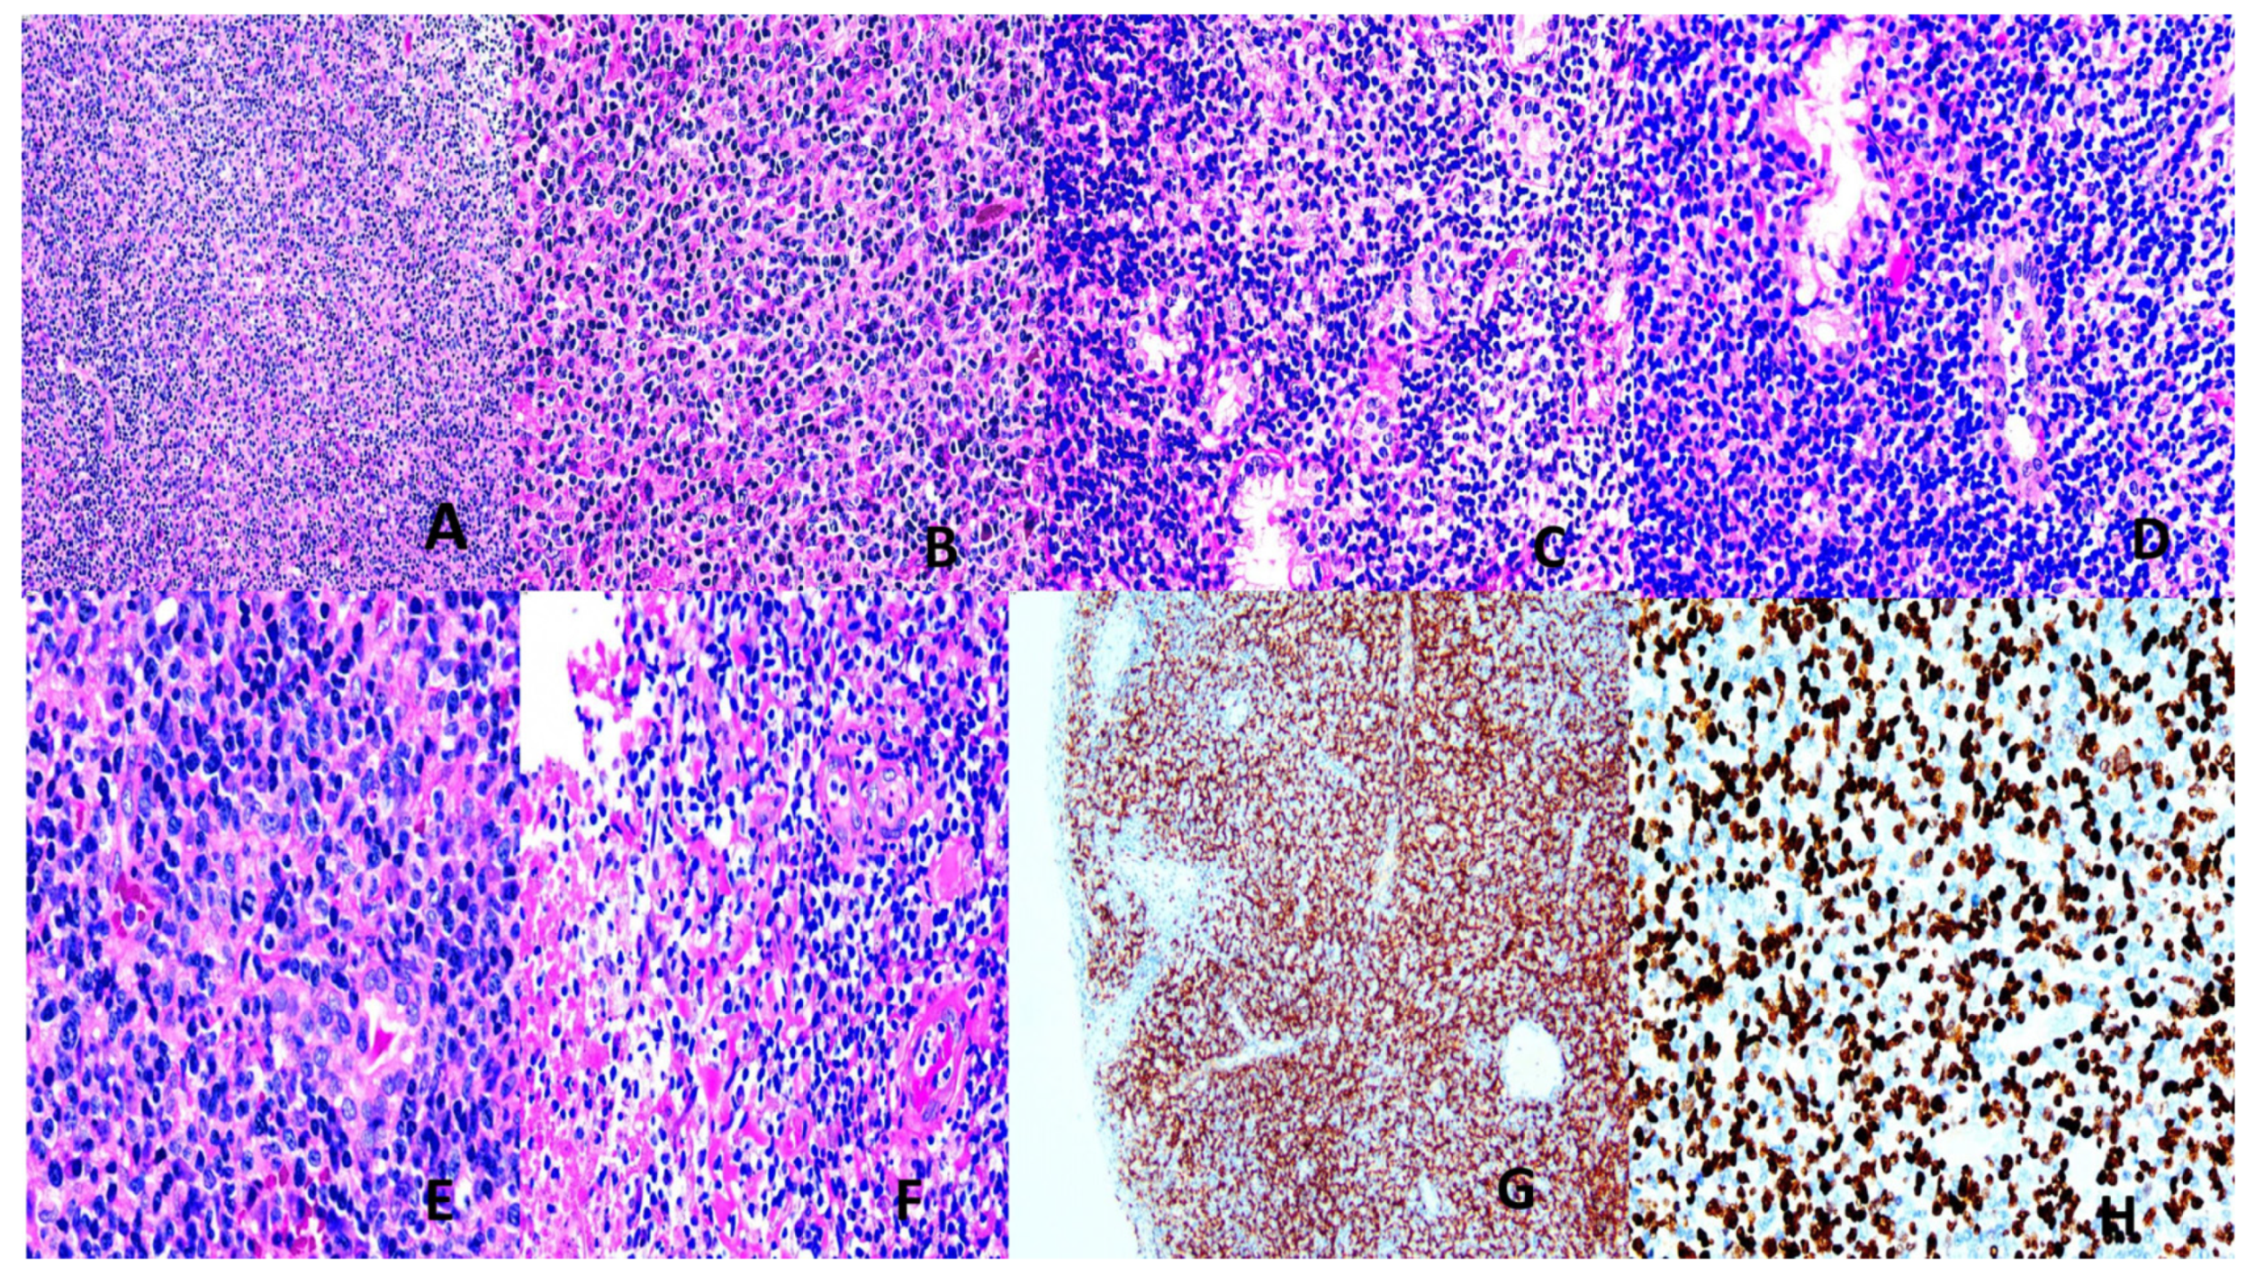

- Burkitt Lymphoma (BL)

- 6.

- Hodgkin Lymphoma (HL)

- 7.

- Extranodal NK/T –cell lymphoma (ENNKTL)

- 8.

- EBV+ Nodal T- and NK-cell Lymphoma (NTNKL)

- 9.

- Systemic EBV+ T-cell Lymphoma of Childhood (SEBVTCLC)

- 10.

- Aggressive NK-cell Leukemia (ANKL)

- 11.

- EBV+ Inflammatory Folicular Dendritic Cell Sarcoma (IFDCS)

- 12.

- Other EBV-associated lymphoproliferative diseases (LPD)

3.2.3. EBV Vaccines